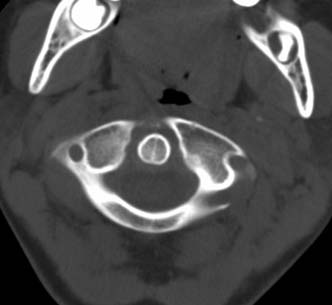

标题: PED0678:男,10岁,寰枢椎平扫。 [打印本页]

标题: PED0678:男,10岁,寰枢椎平扫。

患者在校与同龄孩子打闹后(据家长说被拳击中颈部)出现颈部不适30分钟后入院检查,来时脖子歪斜。请大家看看枢椎齿状突及寰枢关节有问题吗?(3mm层厚断层扫描)。

未见异常

未见明显异常

环枢关节未见异常征象.